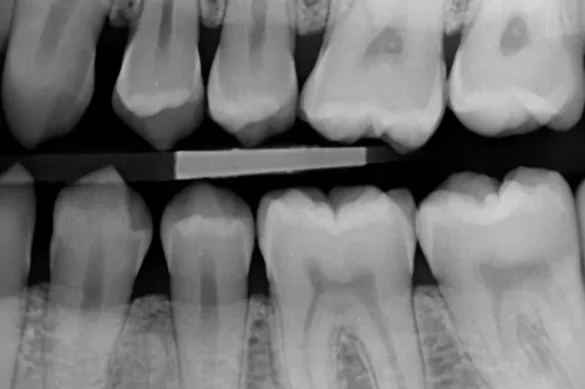

Bitewing X-rays, on the alternative hand, are designed to reveal the top and decrease tooth in a single location of the mouth—from the crown to approximately the extent of the assisting bone. Patients chew down on a wing-fashioned holder, permitting the X-ray to seize the crowns of each the top and decrease tooth simultaneously. This setup makes bitewing movies particularly green for detecting dental caries (cavities) among tooth and comparing the peak of the bone among tooth.

Bitewing X-rays are taken into consideration the gold general for assessing interproximal decay—the type of cavities that increase among adjoining tooth and are tough to come across visually. They also are treasured for tracking adjustments withinside the bone tiers that would suggest gum ailment progression.